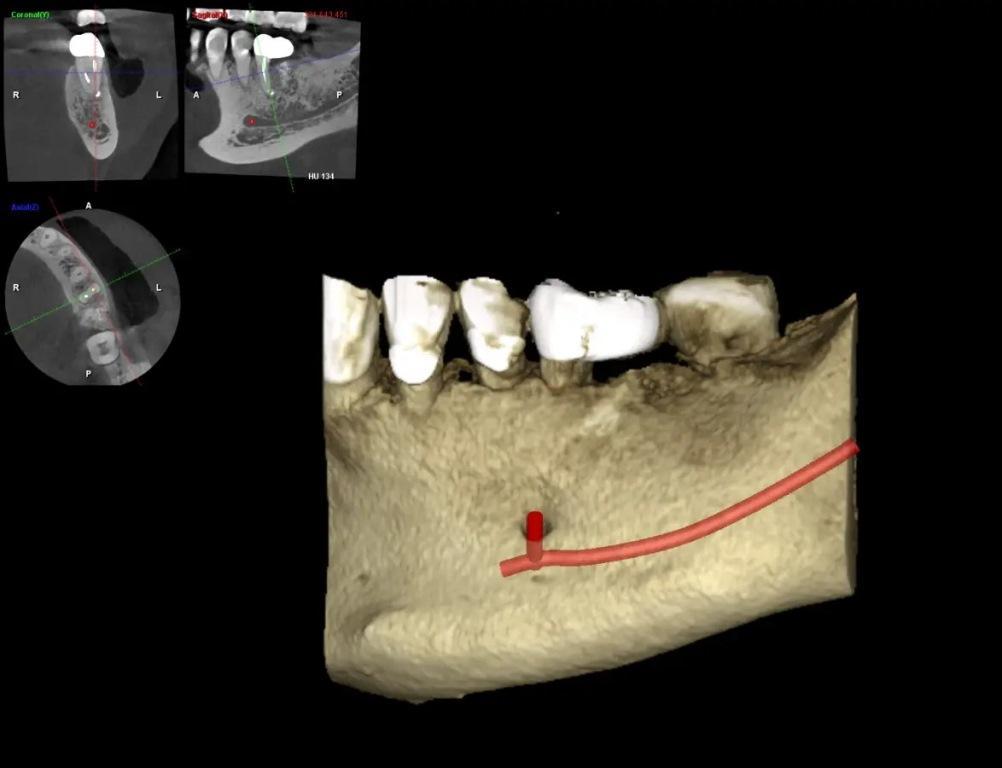

Через год реставрация прошла успешно, и у пациента не было симптомов. Рентгенограммы и контрольная КЛКТ показали полное заживление кости. На периапикальной рентгенограмме зуба была виден здоровый десмодонт (периодонтальная связка) и отсутствие признаков разрушения реставрации (фото 12). Результаты КЛКТ в поперечном, аксиальном и коронарном разрезах показали хорошую ширину и высоту кости и отсутствие патологических изменений (фото 13–16). Окклюзионное сканирование и клинические снимки показали хорошую адаптацию новой реставрации и здоровую десну (фото 17–20).

Фото 13

Фото 14

Фото 15

Фото 16